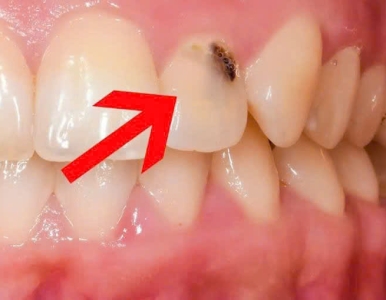

Răng sâu có tự hết không là thắc mắc của rất nhiều người khi thấy răng xuất hiện chấm đen hoặc ê buốt nhẹ. Bài viết từ Nha khoa SV giúp bạn hiểu rõ nguyên nhân, dấu hiệu và cách điều trị sâu răng hiệu quả.

Sâu răng thường bắt đầu âm thầm với các dấu hiệu như hơi thở có mùi, đốm trắng đục hoặc chấm đen trên răng. Tìm hiểu 5 dấu hiệu sâu răng sớm và cách điều trị hiệu quả tại Nha Khoa SV.

Răng sâu là bệnh lý nha khoa phổ biến, có thể gây đau nhức và mất răng nếu không điều trị sớm. Cùng Nha Khoa SV tìm hiểu khi nào nên trám răng sâu, các phương pháp và vật liệu trám tốt nhất hiện nay.

Sâu răng là gì. các giai đoạn và mức độ của sâu răng, Nha khoa điều trị sâu răng uy tín tại quận 3 - Nha Khoa SV